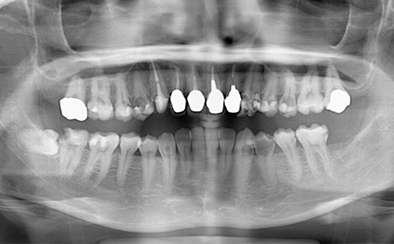

治療前

治療後

黄色い矢印の歯が治療前の対象歯です。レントゲンで観察すると、歯の根のお薬が充分には入っていないようです。

麻酔をして歯の中をマイクロスコープで観察すると、元々あった3つの根だけでなく「もう一つの4番目の根」があったのです。根管治療自体は容易に行えましたが、歯の中を明るく拡大できるマイクロスコープを持っていない歯医者さんでは見つけるのが困難だと思われます。この4つ目の歯の根を治療することにより痛みは消失し「抜歯してインプラント」になるという悪循環に陥らず済みました。根管治療はマイクロスコープを使って精密に、また丁寧に行えば歯を長く保たせることができる治療です。やはり神経自体を残すという選択が、歯の保存にとって一番良いということは間違いありません。